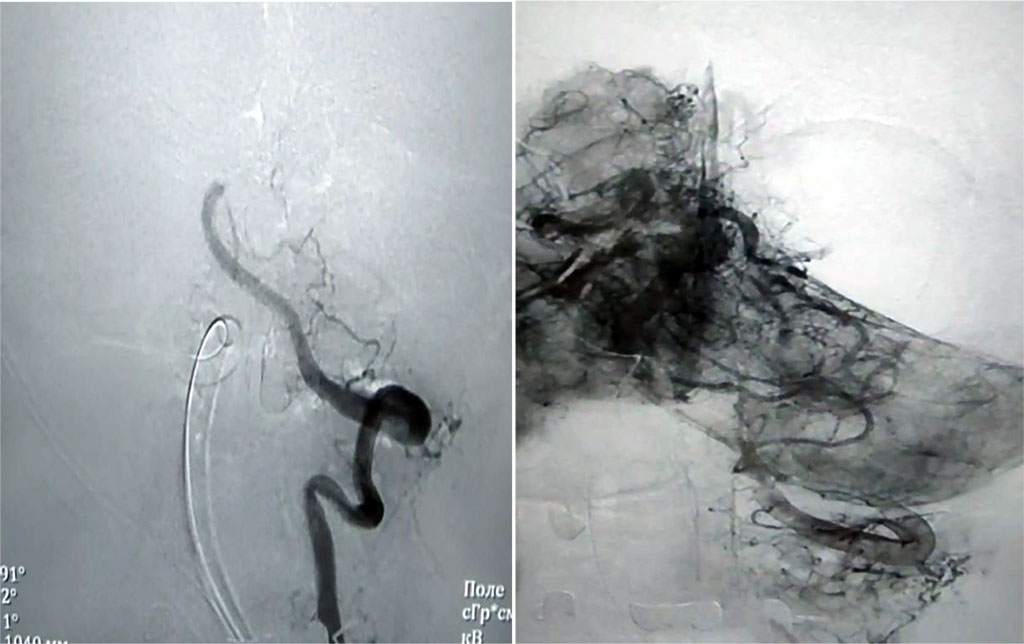

Surgery: Balloon angioplasty and stenting of the left subclavian artery. Surgery record: local anesthesia using Sol. Lidocaini 2% - 2.0 ml. The left radial artery was punctured and catheterized. A 6F introducer was installed. Selective angiography of the brachial and subclavian arteries on the left (where occlusion of the proximal segment of the subclavian artery on the left was detected). Recanalization of the subclavian artery was performed with a 0.35 conductor with the support of a guiding catheter; the conductor was inserted into the descending aorta. Next, an Armada 0.35 8.0x6.0 mm balloon catheter was inserted through a 0.35 hydrophilic guidewire, and predilation of the occlusion zone was performed with a pressure of 6 atm. Next, a 10.0x60 mm Absolute Pro self-expanding stent was delivered, positioned, and implanted using a 0.35 guidewire. Control arteriography of the left radial artery revealed no signs of malposition, proximal or distal dissection. Pressure bandage was applied. The duration of the surgery was 60 minutes.

Figure 1. Angiography of the cranial vessels before surgery

Figure 2. Angiography of the cranial vessels after balloon dilatation and stenting